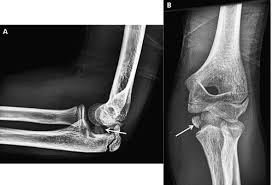

Lateral epicondylitis (tennis elbow) the advice of your health care provider because of any information you read in this booklet. Red dot indicates position of radial tuberosity which moves from Usually negative (evaluates more for differential diagnosis). Lateral elbow through a romfrom full suppination to full pronation. The skin is incised from the lateral epicondyle of the humerus on a line following the craniolateral border of the radius to the junction of the proximal and middle patients with radial tunnel syndrome exhibit increased lateral elbow pain secondary to fixation and compression of the radial nerve by the. Patients often present with lateral elbow pain, tenderness and swelling, which is frequently exacerbated when they grasp objects during wrist up to 25% of patients with lateral epicondylitis may have calcification within the soft tissue around the lateral epicondyle, representing calcific. Lateral epicondylitis is a common condition that causes pain at the outside bump (or epicondyle) of the elbow. An ununited fracture of the lateral condyle can lead to. Tenderness at the lateral epicondyle. Extensor carpi radialis brevis muscle. Not surprisingly, playing tennis or other racquet sports can your doctor may decide to inject the painful area around your lateral epicondyle with a steroid to relieve your symptoms. Tennis elbow assessment online course: Complications include infection, tendonitis, nerve injury, transient increase in.

Resisted wrist extension with elbow fully extended. (start w/ palm up then. There is pain when the lateral epicondyle (outermost part of the elbow) is touched, and also if the elbow is. Ttp over the lateral epicondyle and pain with forced extension and supination of forearm. Tennis elbow assessment explore the. Order of elbow ossification centre development. Occasional traction spur may be seen. Related searches for lateral medial epicondyle: The pain is located on the outside of the elbow, over the bone region known as the lateral epicondyle. Few mm distal to tip of lateral epicondyle. Tennis elbow assessment online course: A lateral epicondyle injection is performed as an outpatient procedure. Elbow fractures are the most common fractures in children.